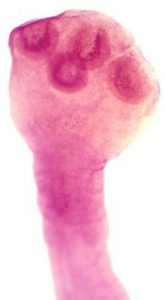

Тениидозы вызывают бычий цепень (Taeniarhynchus saginatus) и свиной цепень (Taenia solium). Бычий цепень — это один из самых крупных глистов размером 4-10 м. Свиной цепень вырастает до 1,5-2 м, а иногда и до 6-ти м. По строению головки (сколекса) и матки эти цепни легко отличить один от другого.

| Фото. А, Б — Бычий цепень (Taeniarhynchus saginatus) на головке имеет четыре присоски и рудиментарный хоботок без крючьев — невооруженный цепень; в матке от срединного канала в обе стороны отходят 18-30 боковых ветвей с яйцами. В, Г — Свиной цепень (Taenia solium) на сколексе имеет четыре присоски и хоботок с двумя рядами крючьев — вооруженный цепень; в матке от срединного ствола в обе стороны отходят 7-10 боковых ветвей, т. е. в 3 раза меньше, чем в зрелом членике бычьего цепня. |

Строение бычьего цепня достаточно простое: взрослая особь состоит из головки (сколекса) с четырьмя присосками и члеников, число которых может доходить до тысячи и более.